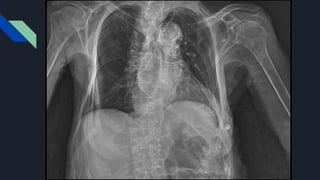

PACIENTE DO SEXO FEMININO, 84 ANOS.

COM INSUFICIENCIA CARDIACA DE GRAU MODERADO TRATADO CLINICAMENTE,

ANGIOPLASTIA DE LESÃO ACENTUADA, DUPLA LESÃO VALVAR AÓRTICA COM

IAO IMPORTANTE , EX TABAGISTA

PACIENTE DO SEXOFEMININO, 84 ANOS. COM INSUFICIENCIA CARDIACA DE GRAU MODERADO TRATADO CLINICAMENTE, ANGIOPLASTIA DE LESÃO ACENTUADA, DUPLA LESÃO VALVAR AÓRTICA COM IAO IMPORTANTE , EX TABAGISTA MEDICAMENTOS DE USO CONTINUOS: - AAS // CLOPIDOGREL // CARVEDILOL 6.25MG 2X // SINVASTATINA 40MG // HIDROCLOROTIAZIDA 25MG // ENALAPRIL 20MG 2X // OMEPRAZOL 20 MG // ANLODIPINO 10 MG // FUROSEMIDA 40 MG // HIDRALAZINA 50 MG // ISOSSORBIDA 20 MG // AAS 100 MG // ESPIRONOLACTONA 50 MG . M.S.S.